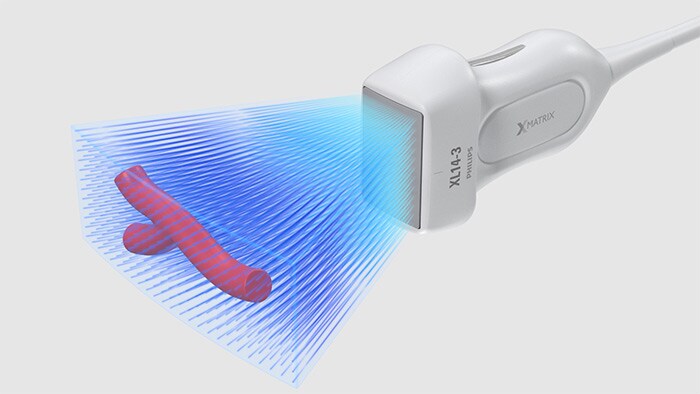

Función 3D/4D sencilla

Asimismo, el XL14-3 tiene capacidad para visualizar la anatomía en asombrosas imágenes 3D/4D mediante un flujo de trabajo sencillo mediante iconos. Los profesionales clínicos pueden ver el interior de un vaso sanguíneo directamente para evaluar la composición y la ubicación espacial de las placas, además de los datos del flujo 3D para estudiar las anomalías relacionadas con la estenosis o la tortuosidad.

La interfaz de usuario 3D/4D también permite generar un modelo de vaso sanguíneo mediante los datos del flujo. El modelado de vasos sanguíneos 3D permite visualizar el flujo de manera directa para realizar un análisis en profundidad de la estenosis o de anomalías relacionadas con la tortuosidad. La ventaja principal: la visualización 3D/4D de la anatomía vascular ofrece una herramienta de comunicación idónea para facilitar las decisiones clínicas entre los proveedores, y también para mejorar las consultas con los pacientes con el fin de ayudarles a comprender su enfermedad.